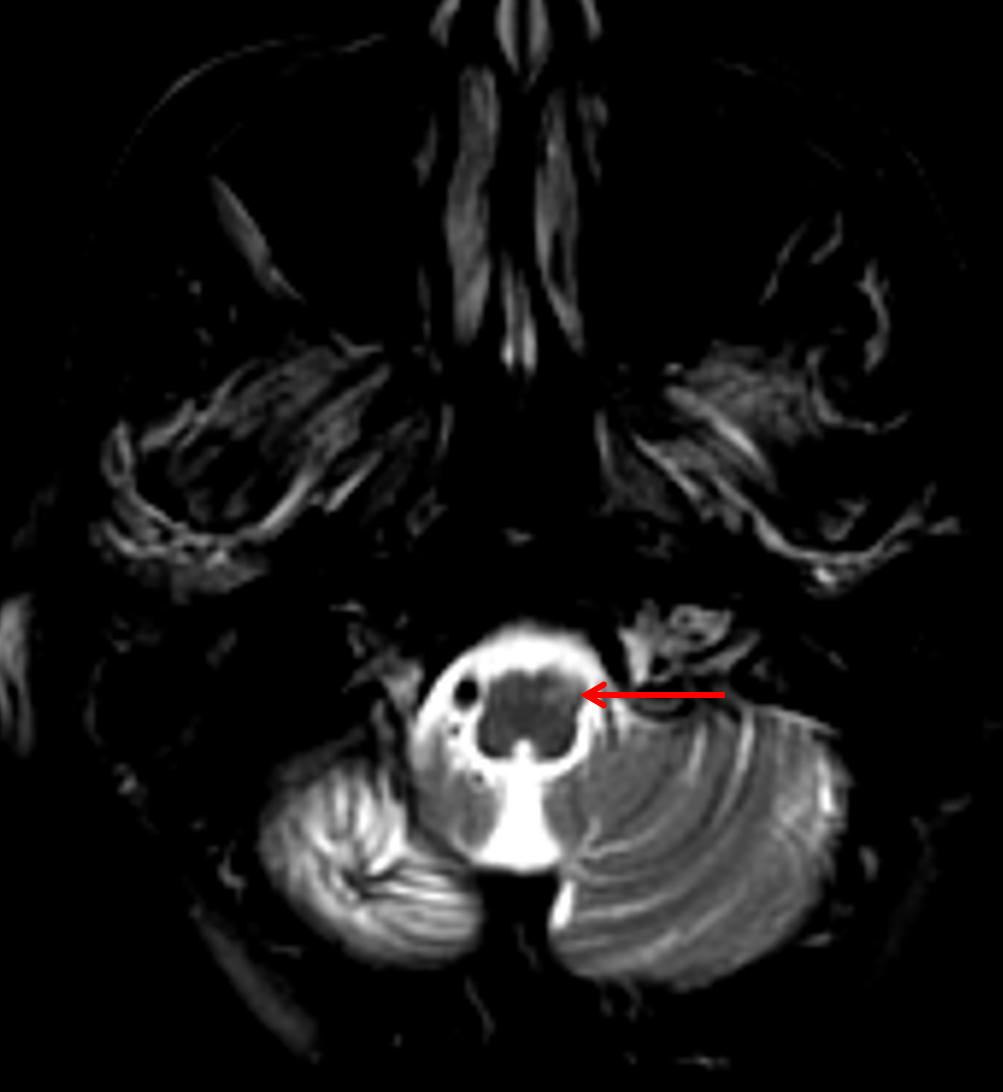

Age: 67

Sex: Female

Indication: Ataxia

Chronic lymphocytic inflammation with pontine perivascular enhancement responsive to steroids (CLIPPERS)